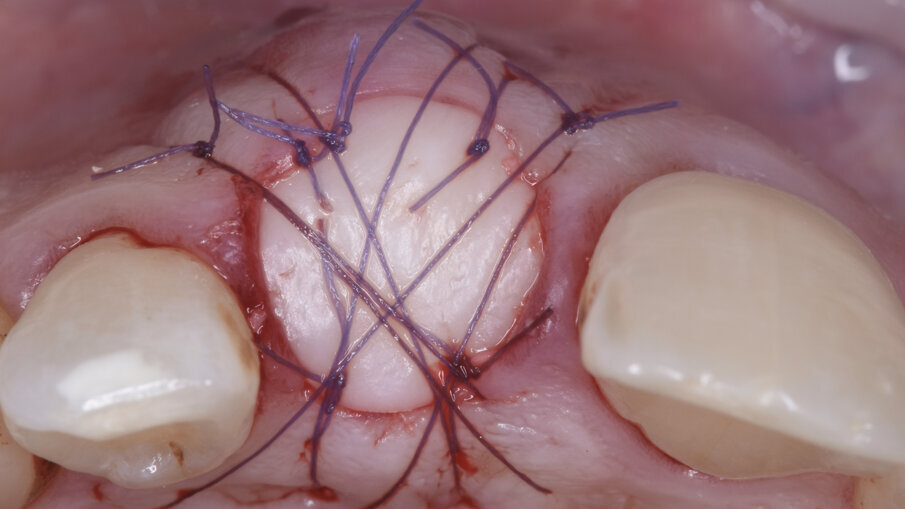

È stata quindi eseguita un’incisione vestibolare intrasulculare del sito senza toccare le papille, facendo scorrere la lama sul piano osseo crestale, e nella porzione più apicale dove era presente la discontinuità della corticale si è spostato la lama mesiale e distale e ancora apicale fino a ritrovare il piano osseo secondo le indicazioni della CBCT; è stato possibile così inserire una membrana in collagene suina Geistlich Bio-Gide (Geistlich Pharma AG, Wolhusen, Switzerland) opportunamente sagomata in modo che avesse un appoggio sui piani ossei (Fig. 4); all’interno dell’alveolo è stato posizionato Geistlich Bio-Oss Collagen (Geistlich Pharma AG, Wolhusen, Switzerland), osso bovino deproteinizzato con un 10% di collagene suino addizionale, materiale osteoconduttivo che oltre a essere mantenitore di spazio e scaffold per la rigenerazione ossea, funge anche da sostegno per il tessuto molle soprastante (Fig. 5). Si è quindi proceduto dopo anestesia palatale a un prelievo tramite bisturi circolare di un punch epitelio connettivale di forma tondeggiante e misure simili all’alveolo dell’1.1 da sigillare; dopo la disepitelizzazione dei margini dell’alveolo si è proceduto alla sutura del punch al di sopra del sostituto osseo con suture Vicril 6-0 (Johnson & Johnson Medical Spa, Pomezia RM, Italia) con punti staccati alle quattro estremità e sutura a materassaio esterno incrociato compressiva (Fig. 6). In questa fase la paziente è stata riabilitata con un maryland bridge in composito cementato adesivamente.

Dopo anestesia plessica con articaina 1:100.000, senza incidere le papille mesiali e distali, viene delicatamente estratto l’1.1 con strumenti piezoelettrici preservando la corticale buccale presente (indispensabile per la gestione della chirurgia); dopo un’attenta toeletta chirurgica del sito si è proceduto ad una Ridge Augmentation con Socket Seal.